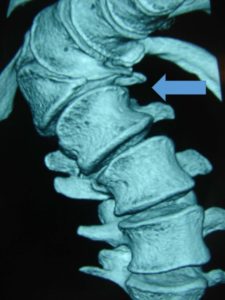

Εικόνα 8 : Τρισδιάστατη (3-D) αξονική τομογραφία της Θωρακοοσφυϊκής Μοίρας της Σ.Σ. Μετωπιαία προβολή. Παρατηρείται η ύπαρξη ημισπονδύλου συνεπεία του οποίου προκλήθηκε η σημαντικοτάτη σκολιωτική παραμόρφωση της Σ.Σ. με το κυρτό προς τα δεξιά (βέλος). Διαπιστώνεται επίσης σημαντική ασσυμετρία των πλευρών. Οι πλευρές στο δεξιό μέρος του κυρτώματος είναι ιδιαίτερα λοξές σε σχέση με την Σ.Σ. ενώ οι φέρονται σχεδόν οριζόντια.

Εικόνα 10 : Απλή ακτινογραφία παρατηρούνται:

Ι. Ατελής διαχωρισμός των σπονδύλων δεξιά και οστική γέφυρα

που συνδέει τους σπονδύλους του κυρτώματος.

ΙΙ. Έλλειψη 4 πλευρών δεξιά.

ΙΙΙ. Θωρακική σκολίωση.